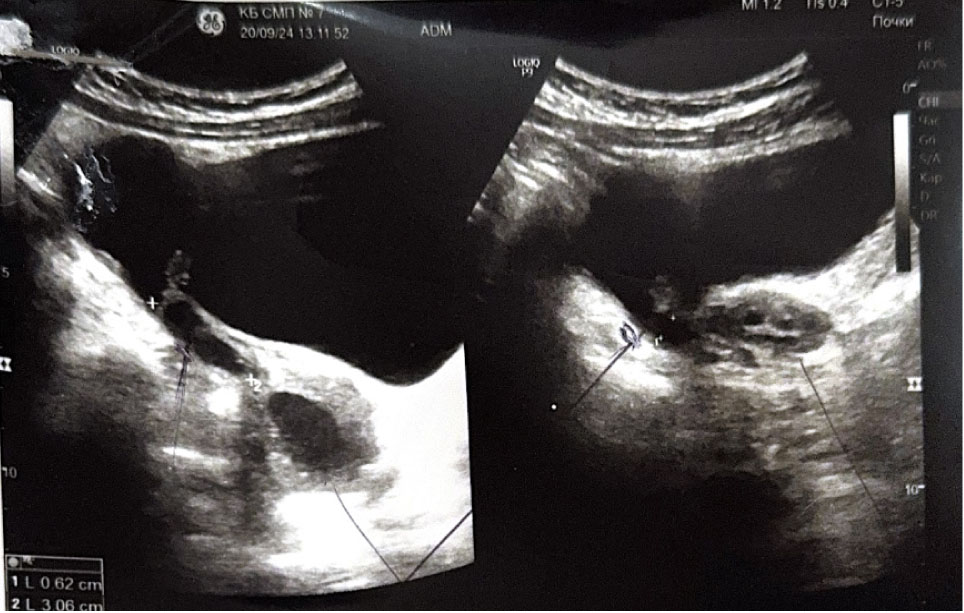

При госпитализации пациентке выполнено УЗИ органов малого таза, выявлено: тело матки смещено вправо, размеры 37 × 26 × 28 мм, миометрий однородной структуры. Толщина эндометрия 3–4 мм, соответствует фазе пролиферации. Правый и левый яичники визуализируются, нормальных размеров без структурных изменений. Слева от матки образование 45 × 42 × 47 мм, средней эхогенности с ровными контурами, соответствует структуре миометрия, толщиной 15–17 мм. В центре образования жидкостной однородный участок, размерами 29 × 30 мм (гематометра?). Выше и каудальнее левого яичника лоцируется тубулярное анэхогенное образование толщиной 4–6 мм протяженностью 30 мм (маточная труба?). Заключение: аномалия развития матки (матка с рудиментарным рогом слева). Гидросальпинкс слева. Гематометра слева (рис. 1, 2).

Рис. 1. Ультразвуковое исследование органов малого таза. Аномалия развития матки

Рис. 2. Ультразвуковое исследование органов малого таза. Рудиментарный замкнутый рог матки